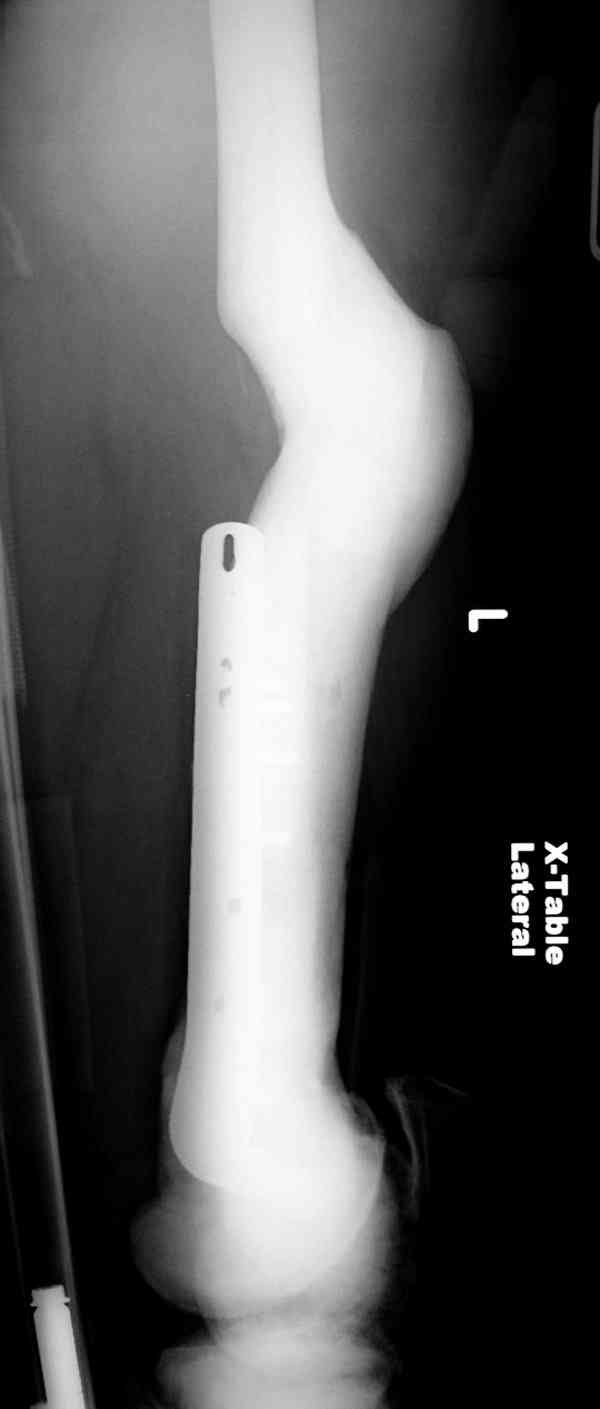

Что-то пациенту как-то не везет по жизни... Тоже самое - интрамедуллярный остеосинтез коротким штифтом для проксимального отдела бедра. Ранняя нагрузка сразу...

Здесь у меня дополнительные снимки с большим разрешением и в разных режимах, а то те дигитал снимки совсем очень блеклые, может, эти изображени изменят выбор тактики

После неудачной попытки скелетного вытяжения в первом мед.учреждении, после осмотра снимков и изучения истории, поставили диагноз “Остеопетроз” или мраморная болезнь, редкая наследственная костная паталогия, где имеется нарушение формации остеокластов.

Конечно, было бы идеальным применение интрамедуллярного остеосинтеза, но учитывая прежний собственный опыт (лечил перелом бедра) и

публикации, предупреждающие о трудностях при обработке кости (иногда из-за неподготовленности инструментария результатом была неадекватная фиксация перелома, или перенос операции из-за фактора усталости оперирующего персонала), решили применить пластину (и в этом же случае был выбран Synthes plate, так что представитель за два дня

зароботал... на десерт тоже).

Заказаны были дополнительные различные дрели, и на следующий день, усиленной бригадой, больного прооперировали, потратив на каждое отверстие около 25-35 минут, хотя сверлили с охлаждением по нарастающей по диаметру сверл и с их заменой каждые 2 мм сверления.

Теперь стоит задача со сращением перелома, из-за отсутствия литературных данных по применению костных стимуляторов при остеопетрозе, и не зная как поведет в этой среде Grafton, все таки надеюсь, что даст толчок к стимуляцию, решил применить пастообразную деминерализованную костную матрицу, расположив спереди между отломками.